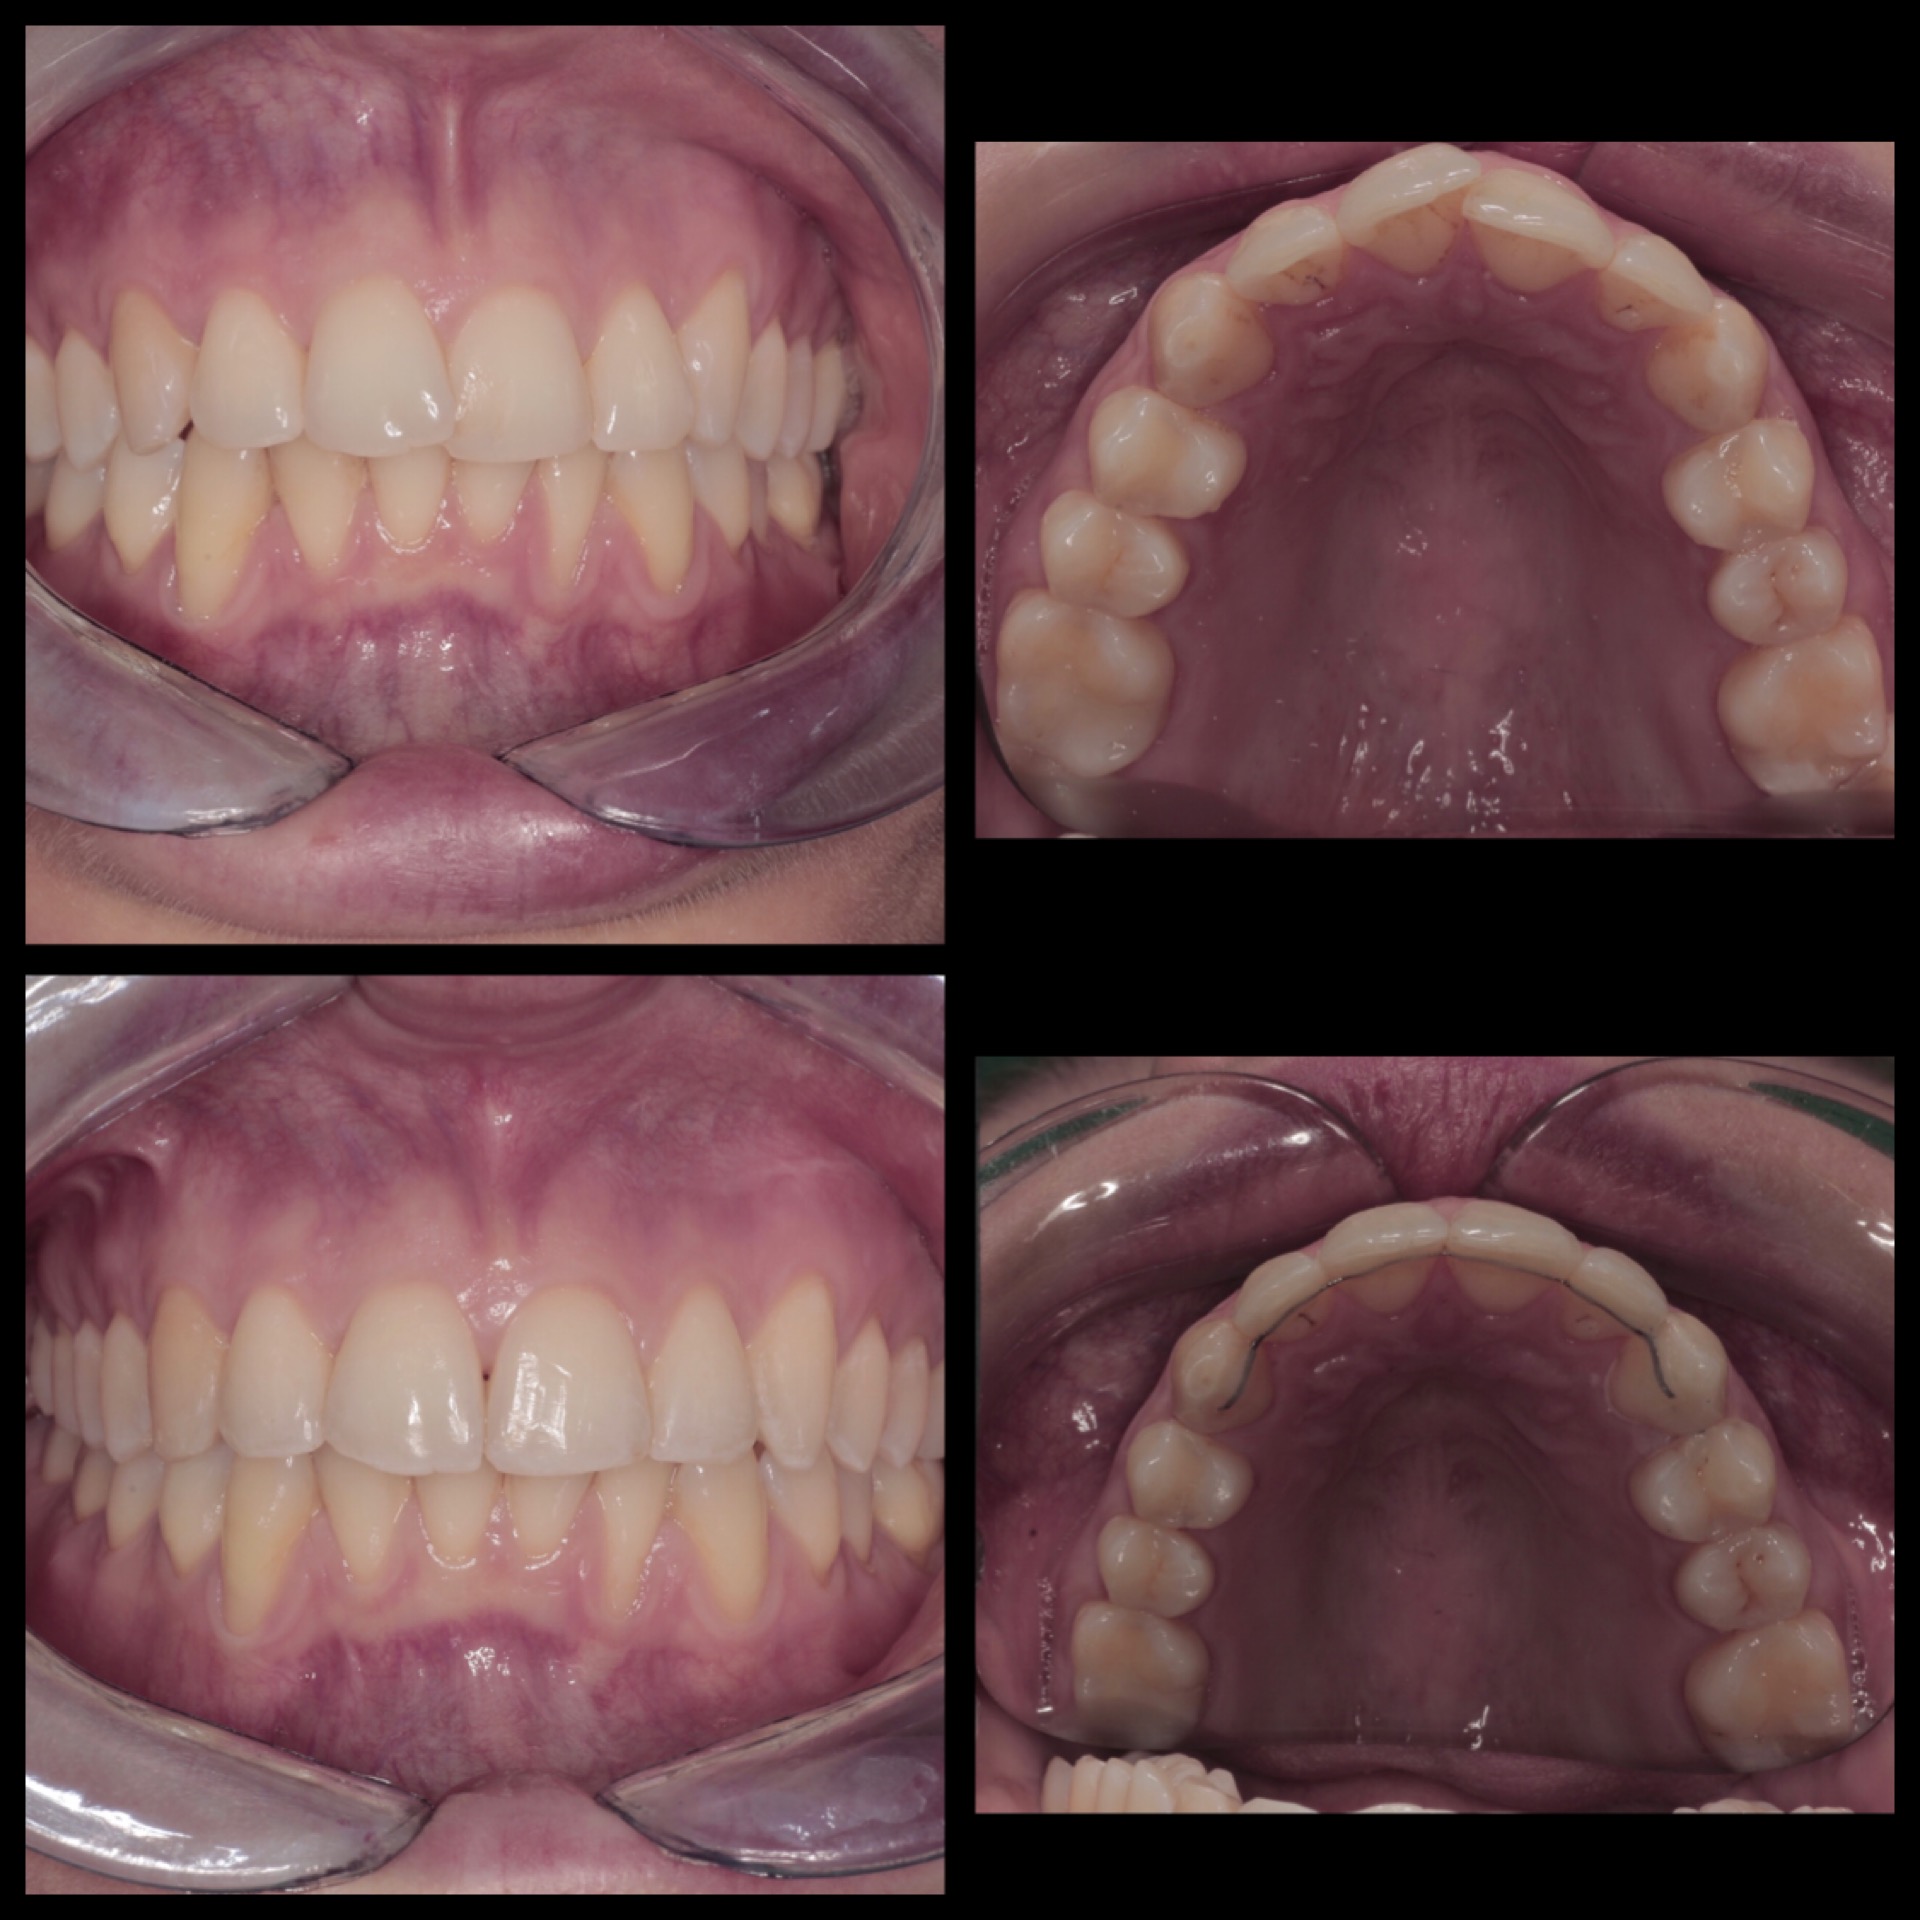

Con l’ortodonzia invisibile è possibile migliorare la propria immagine senza gli svantaggi di brackets e fili tradizionali ma con la stessa efficacia ed efficienza dell’ortodonzia convenzionale.

Mediante una serie di allineatori trasparenti e rimovibili, l’ortodonzia invisibile sposta i denti nel loro corretto allineamento settimana per settimana e, molto spesso, in meno tempo rispetto ai sistemi tradizionali.